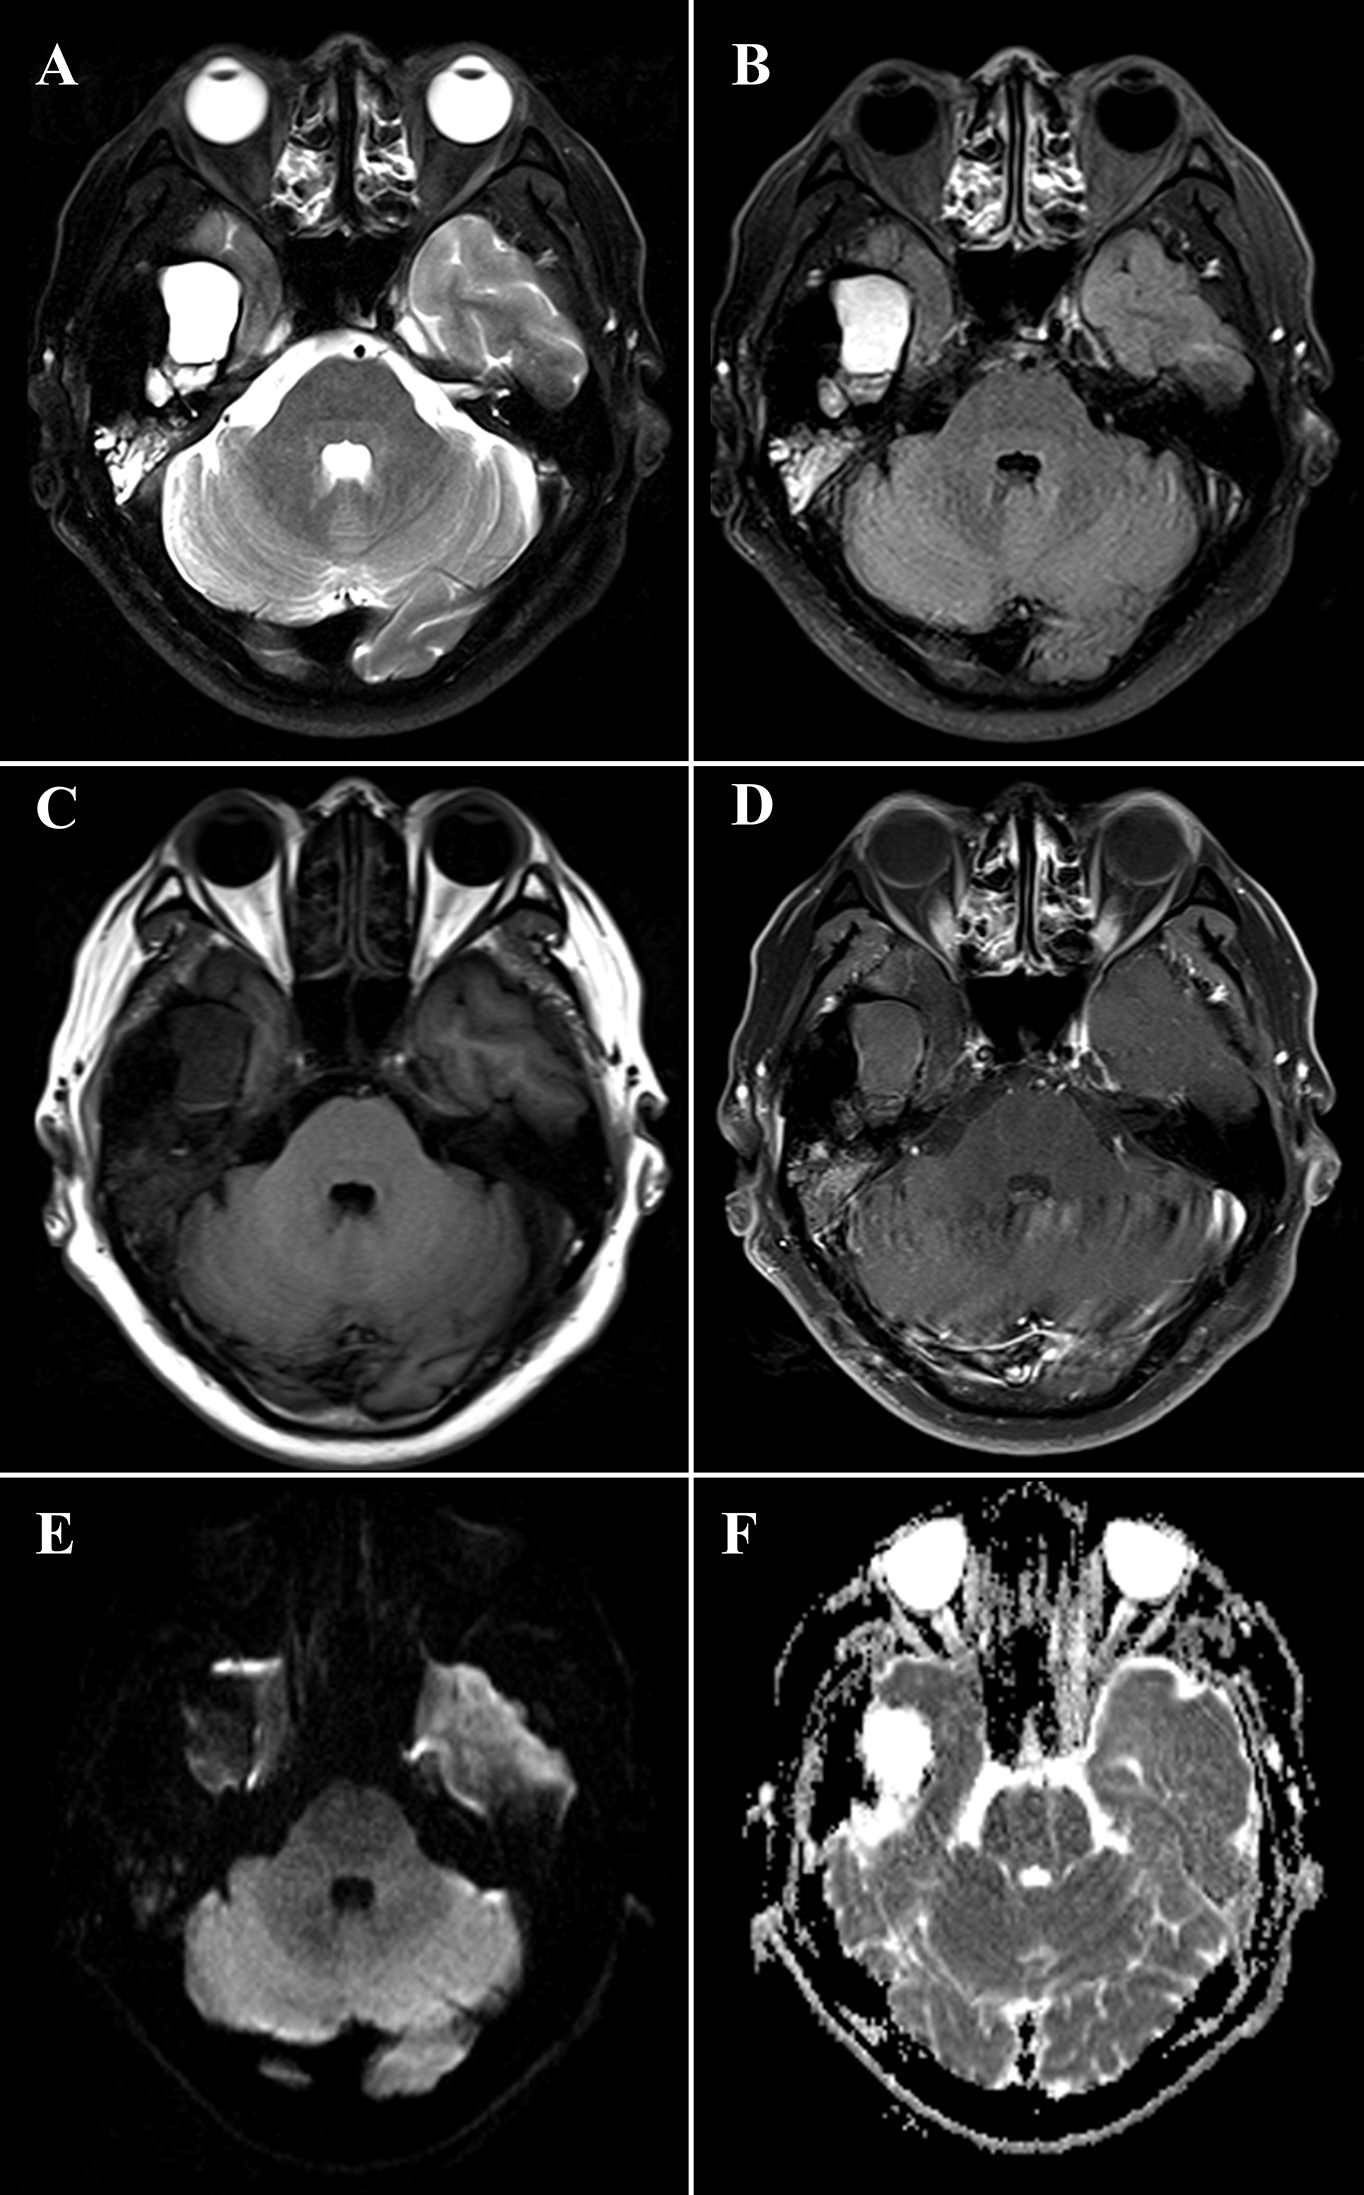

The HRCT revealed a mixed-density mass with soft tissue density and slightly hypodensity (5.2 cm × 3.2 cm × 3.3 cm) in the right temporal squama. Incomplete bone shell was visible, and the articular surface of temporal bone was eroded while the condylar head was not involved (Figure 1). The fossa media was invaded through the defective temporal bone, and the temporal lobe was compressed. MRI plan scan identified an irregular and heterogeneous mass, which showed cystic components with slightly hypointensity in T1-weighted imaging (T1WI), water-like hyperintensity T2-weighted imaging (T2WI), and solid components with hypointensity both T1WI and T2WI (Figure 2). Hypointense signal was observed on diffusion-weighted images (DWI) (Figure 2). After contrast agent (Gd-DTPA) administration, slightly enhancement was present at the wall of the cystic part, no enhancement was observed in the solid part (Figure 2). The effusion was also observed in the adjacent mastoid.

Figure 2

Magnetic resonance imaging (MRI) of a 48-year-old man with diffuse tenosynovial giant cell tumor (D-TSGCT) in right temporomandibular joint (TMJ). MRI reveals a predominantly hypointense lesion with focal cystic changes on T2-weight imaging (A), fluid-attenuated inversion recovery (FLAIR) sequence (B) and T1-weighted imaging (C), which infiltrates the medial cranial fossa. Mild enhancement at the wall of the cystic part and no enhancement of the solid part was observed after administration of contrast agent (D). The lesion is hypointense on diffusion-weighted imaging (DWI) (E) and displays heterogeneous intensity on the apparent diffusion coefficient (ADC) map (F).

CT and MRI provide valuable information in the diagnosis and developing treatment plan of D-TSGCT, delineating the extent of lesion as well as destruction of bone (20). Classical radiological features of the disease include high-density noncalcifying soft tissue mass on CT owing to extensive iron deposition (20). The MRI presentation of lesion varied according to the component proportions of hemosiderin, lipids, fibrous, stroma, and cellular elements (21). The lesion usually generates a low to intermediate signal in both T1WI and T2WI because of the paramagnetic effect caused by hemosiderin concentration (22). The low signal intensity caused by the presence of hemosiderin on MRI that is accentuated on gradient-recalled echo (GRE) or susceptibility-weighted imaging (SWI) sequences is also termed as the “blooming effect” (23), which is a typical feature of D-TSGCT. All these typical features are also prominent in our present case. Comparing to the lesion in the large joints which commonly involve both sides of the joint and affect joint cavity or surrounding soft tissues, the D-TSGCT in the TMJ can be centered in the bone and leads to destruction of the mandibular condyle, temporal bone, and intracranial extension (9). Cyst formation with water-like hyperintense signal at T2WI can be observed at the edge of the lesion in some cases, with non or minimal wall-like enhancement (3). Consistently, the present case manifested as heterogeneous mass centered at the temporal bone, and lateral cyst was also observed. It is worth noting that, uniquely, condylar head was preserved in this lesion.